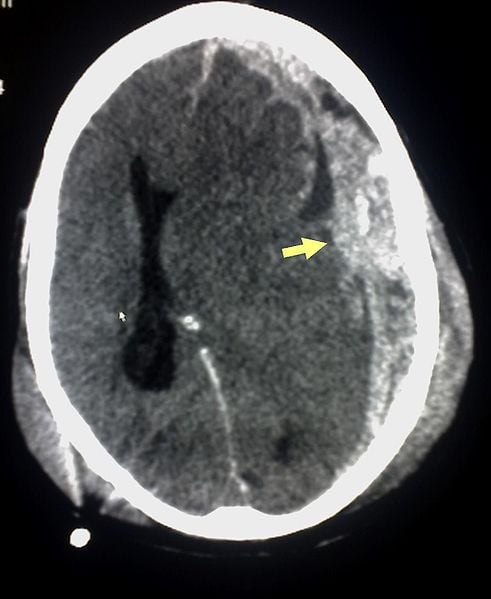

Researchers evaluated the pathological impact of both single incident TBI, such as those sustained during combat, and mild, repetitive TBI, commonly seen in boxers and football players. They hoped to better understand what measures need to be taken in order to identify risk, early instances of TBI and to reduce long term complications.The image is a CT scan of a subdural hemorrhage caused by traumatic brain injury.

Image Source: The CT scan of a subdural hemorrhage resulting from TBI is available in the public domain.